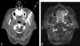

Enlarged lateral retropharyngeal lymph node